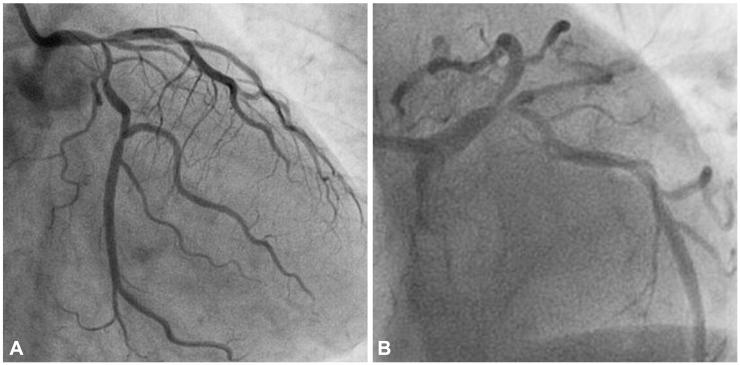

冠状动脉内导丝断裂并遗留纤维丝导致致命性亚急性支架内血栓形成。

Fatal subacute stent thrombosis induced by guidewire fracture with retained filaments in the coronary artery.

During percutaneous coronary intervention, guidewire fractures are very exceptionally encountered in medical practice, but can cause fatal complications such as intracoronary thrombus formation, embolization and perforation. Removal of the remnant segments of guidewire is important for the prognosis. There are several methods being recommended for the treatment of fractured guidewire remnants. However, the best treatment of remnant guidewire filament is still unclear. Herein, we present a case where we did not completely remove remnant guidewire filaments that caused fatal coronary thrombosis.

摘要

在经皮冠状动脉介入治疗中,导丝断裂在医学实践中非常罕见,但可导致致命并发症,如冠状动脉内血栓形成、栓塞和穿孔。取出残余的导丝段对于预后很重要。目前有几种方法推荐用于治疗断裂的导丝残余物。然而,残余导丝丝的最佳治疗方法仍不清楚。在此,我们报告了 1 例未完全取出残余导丝丝导致致命性冠状动脉血栓形成的病例。